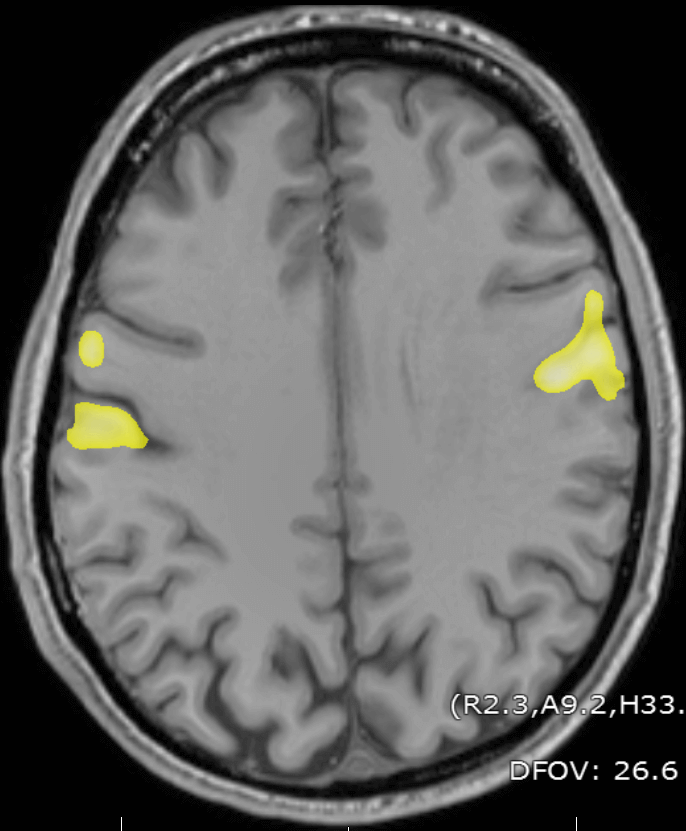

Tongue movement generates BOLD signal changes more ventrally on the motor homonculous, as seen below:

fMRI signal generated by tongue movement

fMRI changes from tongue movement